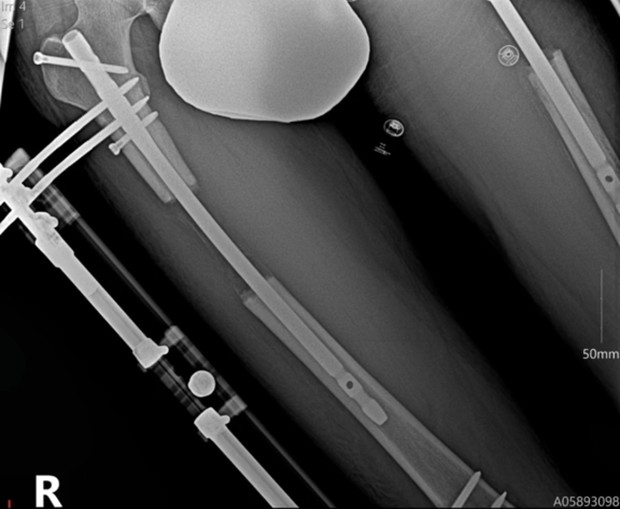

Dynzell Sigers pun mantap melakukan operasi pemanjangan tungkai kaki demi meningkatkan kepercayaan dirinya. Operasi ini dilakukan dengan menambah panjang tulang di lengan atau kaki pasien sekaligus meregangkan otot, tendon, dan ligamen di sekitarnya.

Selama operasi, dokter memotong tulang menjadi dua segmen lalu memasang external fixation pada kedua segmen tulang. Secara bertahap kedua ujung tulang dipisahkan sehingga merangsang tulang baru untuk tumbuh dan mengisi celah yang tercipta. Proses ini memerlukan waktu hingga dua bulan lamanya.

Pasien yang menjalani operasi pemanjangan tungkai tidak akan bisa langsung berjalan. Mereka membutuhkan terapi fisik dan okupasi untuk memulihkan kemampuan berjalan. Untuk mencapai kondisi pulih sempurna, pasien bisa menghabiskan waktu hingga satu tahun.